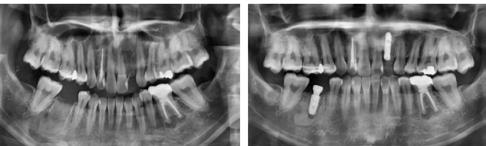

1. ábra: Dr. Jung 10 éves kontrollal rendelkező 4.7-es helyén levő Dentium short implantációja. Preoperativ CT, ínyformázó 4 hónappal a műtét után, valamint 4 hónap múlva 4.7-es szólókorona.

2. ábra: Dr. Park esete. 4.6-os fogon levő jelentős csontfelritkulás röntgenképe, extractio és iGBR alkalmazása Osteon Xenoval. 4 hónap múlva Dentium short implantátum, majd 4 hónap múlva korona készítése.

3. ábra: Dr. Han esete. 2.4-2.5-2.6 lokalizációban keskeny gerinc. Csontpótlás Osteon Xeno- val, majd 4 hónap múlva 3 db Dentium short implantátum behelyezése. 4 hónappal később protetikai munka.

4. ábra: Dr. Chung esete. Short implantátumok 10 éves kontrollja a 4.7 és 1.6-1.7 lokalizációban.

5. ábra: Dr. Chun esete. Dentium Narrow implantátumok és azok protetikai ellátása 4 hónappal a beültetést követően.

6. ábra: Dr. Lim esete. Dentium Narrow implantátumok a felső állcsonton, guide tervezés, ideiglenes hídpótlás azonnali terheléssel, majd 4 hónappal később végleges protetikai ellátás.